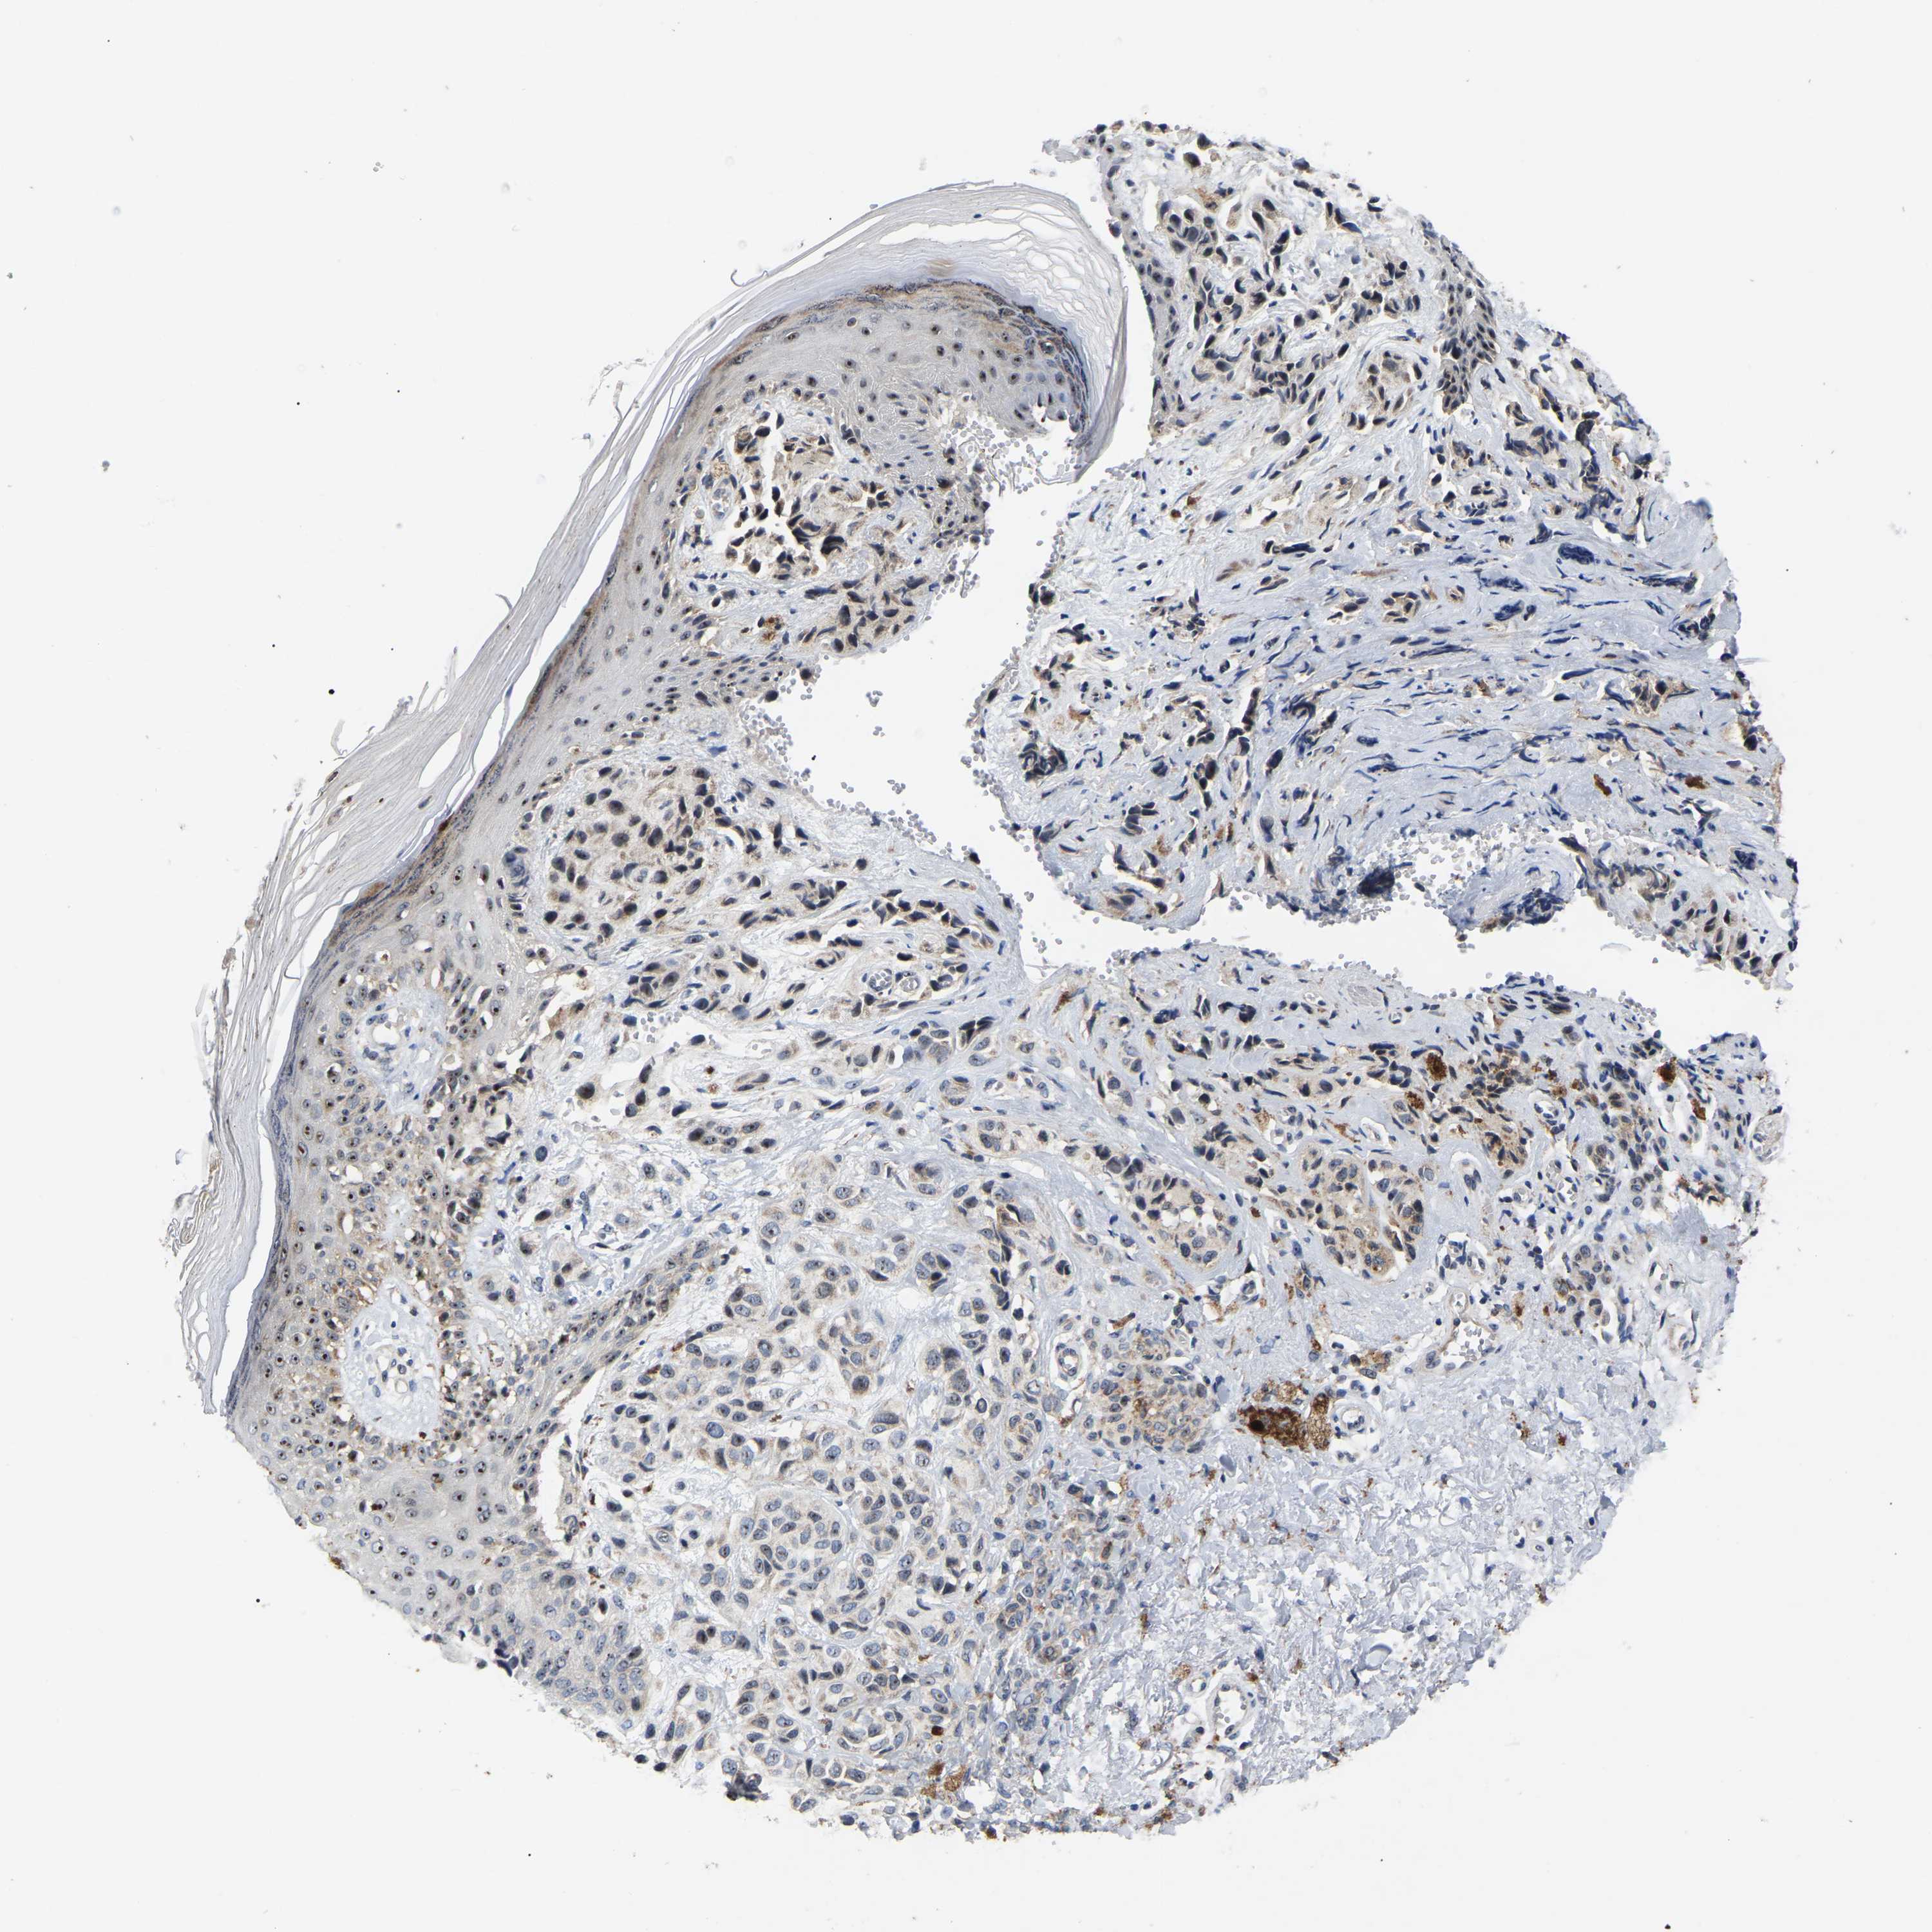

MELANOMA - Protein expressioni

A mouse-over function shows sample information and annotation data. Click on an image to view it in a full screen mode. Samples can be filtered based on level of antibody staining by selecting one or several of the following categories: high, medium, low and not detected. The assay and annotation is described here.

Note that samples used for immunohistochemistry by the Human Protein Atlas do not correspond to samples in the TCGA dataset.

Antibody stainingi

Antibody staining in the annotated cell types in the current human tissue is reported as not detected, low, medium, or high, based on conventional immunohistochemistry profiling in selected tissues. This score is based on the combination of the staining intensity and fraction of stained cells.

Each image is clickable and will lead to virtual microscopy that enables deeper exploration of all samples and also displays staining intensity scores, fraction scores and subcellular localization as well as patient and tissue information for each sample.

Antibody HPA018999

Staining

High

Medium

Low

Not detected

Intensity

Strong

Moderate

Weak

Negative

Quantity

>75%

75%-25%

<25%

None

Location

Nuclear

Cytoplasmic/membranous

Cytoplasmic/membranous,nuclear

Malignant melanoma, NOS

Malignant melanoma, Metastatic site